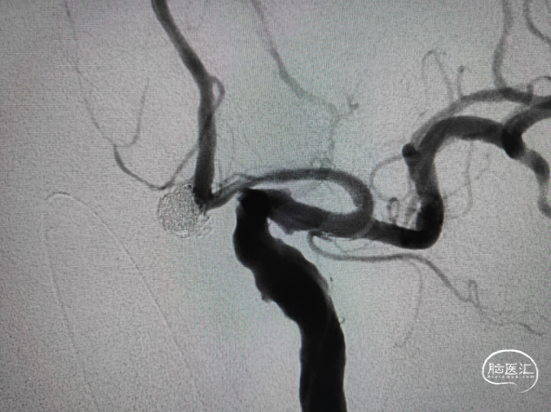

6mm*20cm 通桥凤®弹簧圈成篮,5mm*15cm、4mm*12cm、3mm*8cm 通桥凤®弹簧圈严密填塞瘤体及下方2个子瘤,子瘤填塞完全依靠弹簧圈寻空能力,栓塞效果可。

填入2mm*4cm、1.5mm*3cm 通桥凤®弹簧圈2枚,弹簧圈顺利填入子瘤。

术后正侧位,动脉瘤栓塞满意,载瘤动脉血流通畅,未行支架或微导管辅助栓塞。